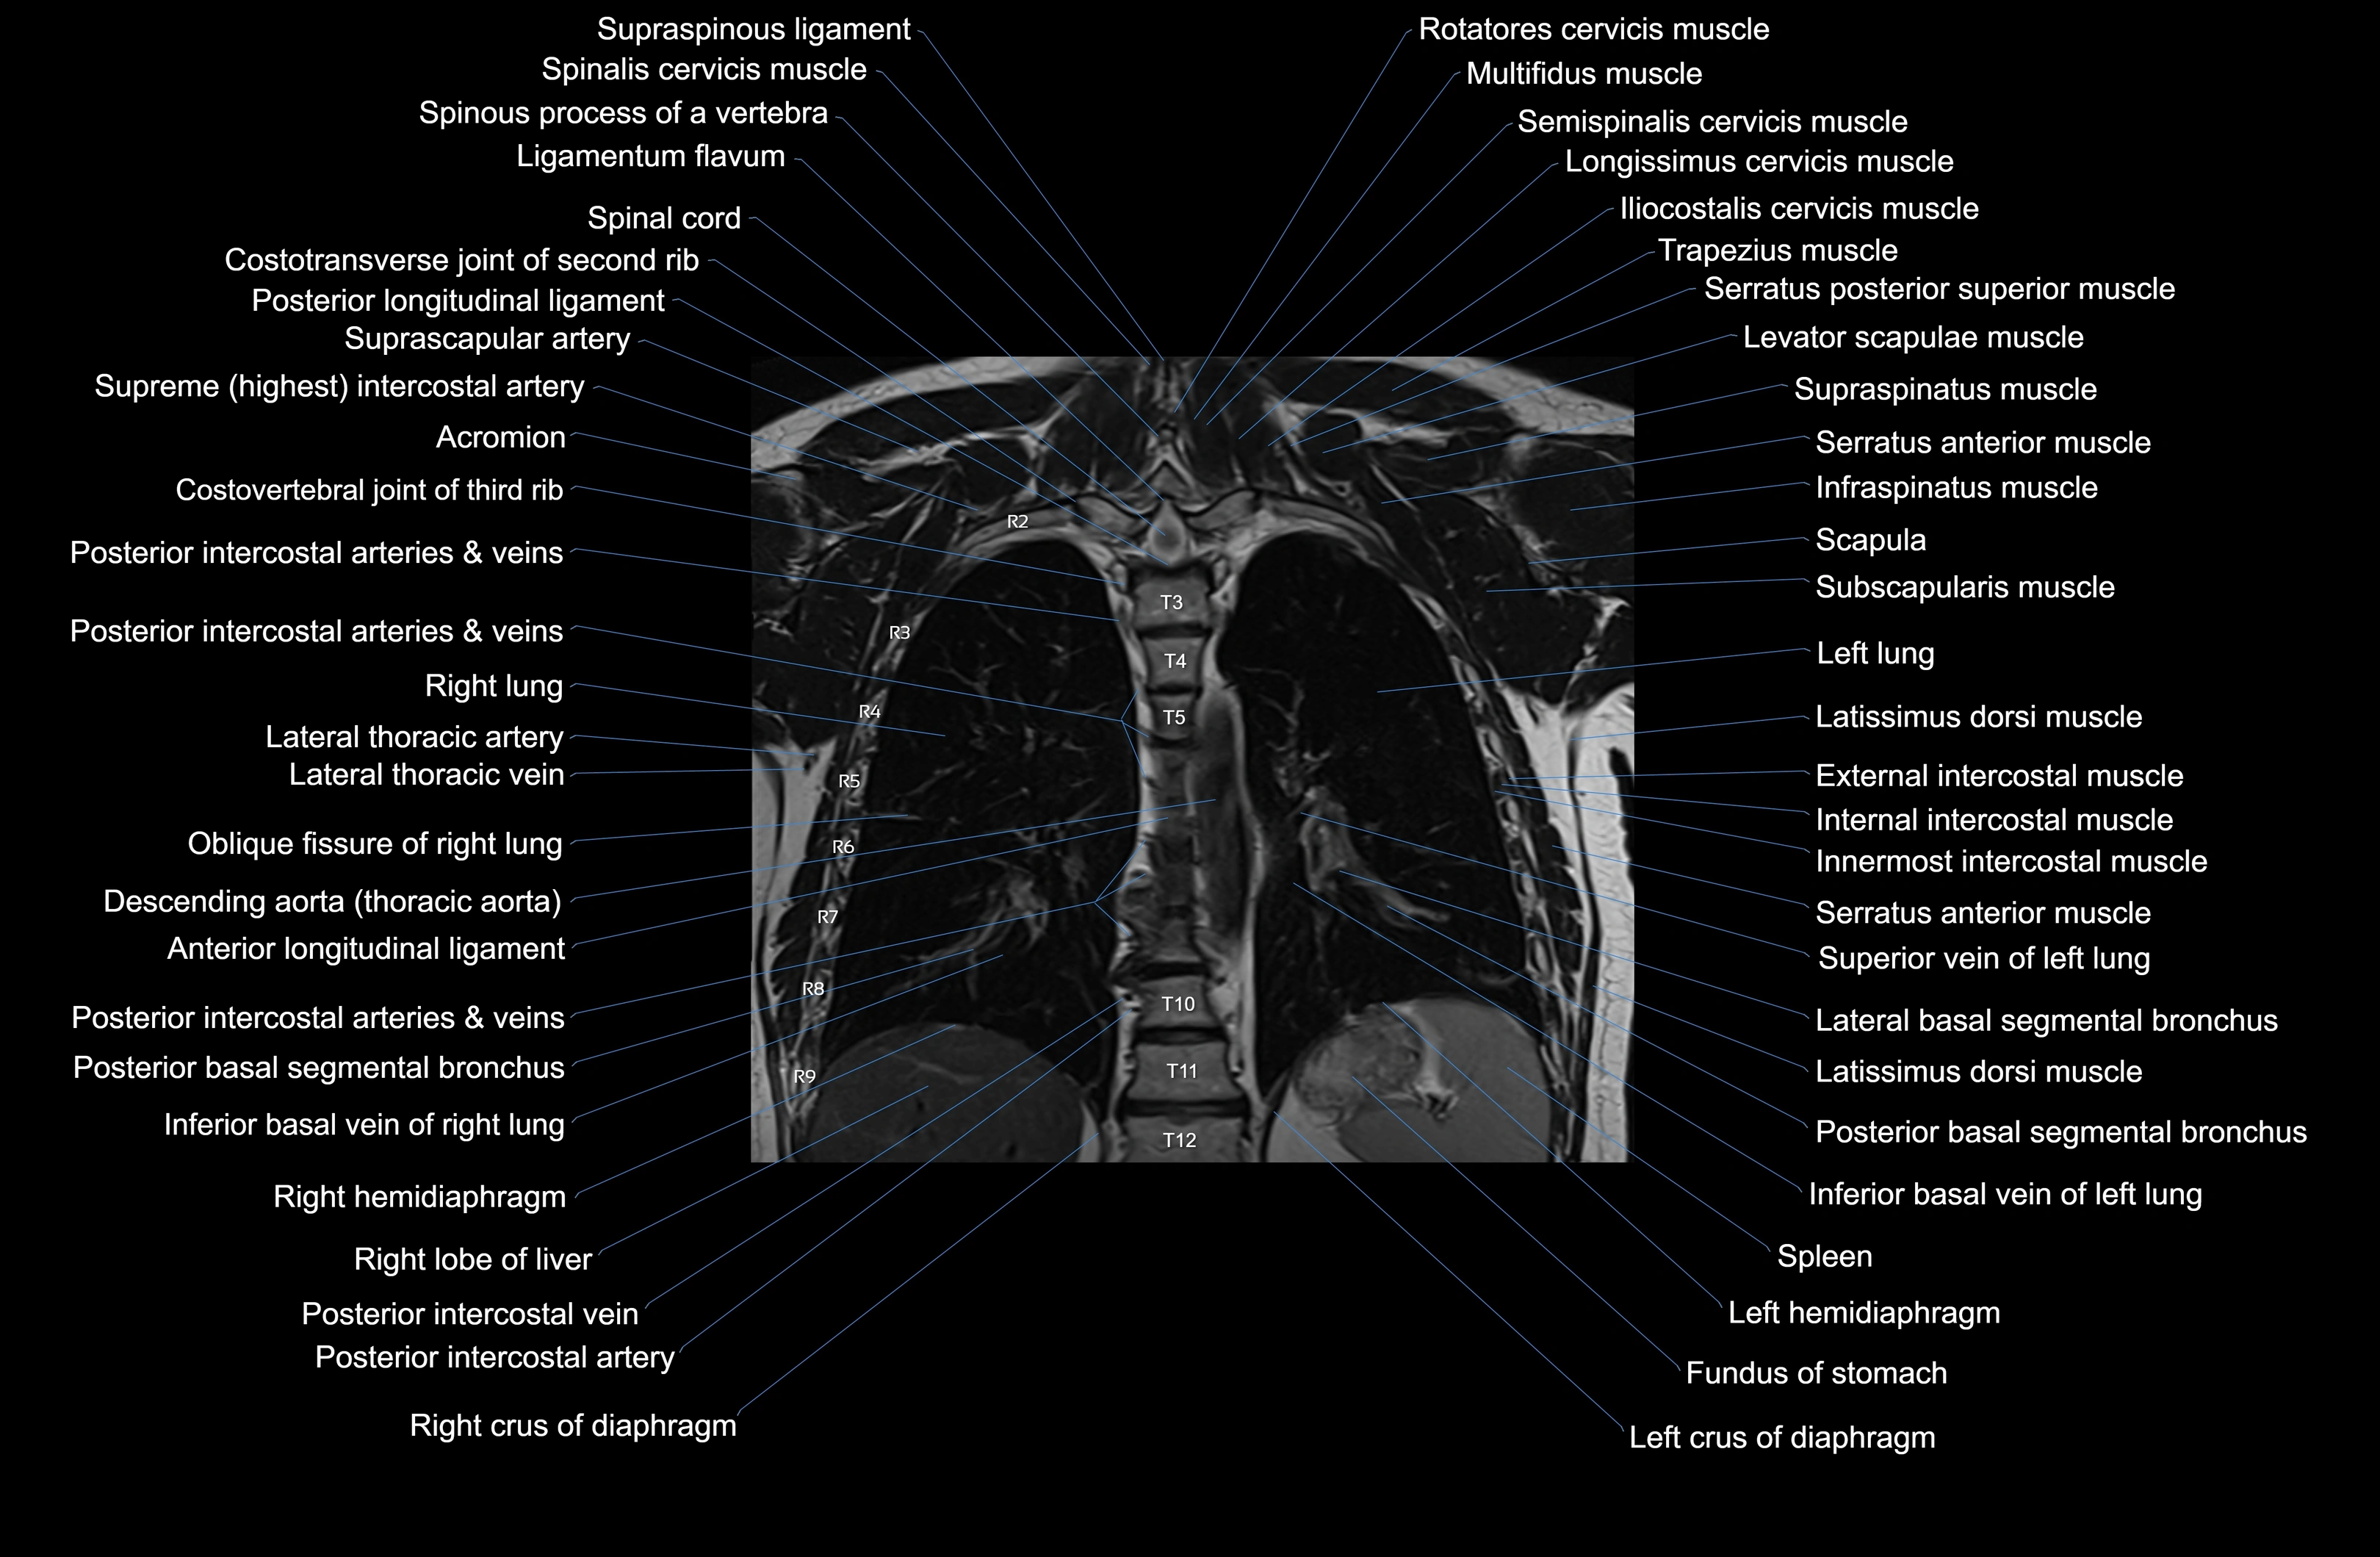

MRI images